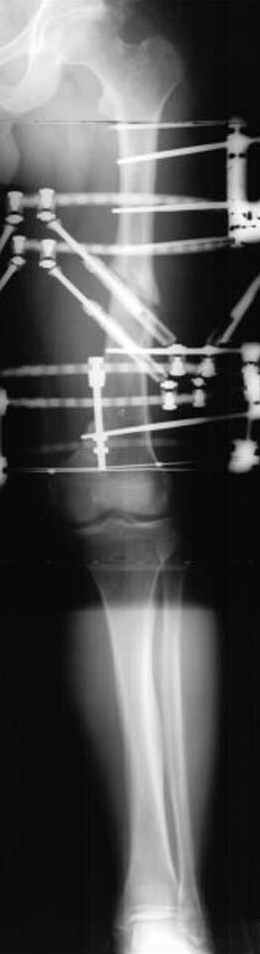

Несколько снимков из моей коллекции, чтобы разьяснить, почему мы до сих пор делаем различные варианты остеотомии.

На рисунке N1 предоперационный план лечения ложного сустава шейки бедра- линия ложного сустава, угол и направление введения импланта, клиновидная остеотомия в градусах и миллиметрах, второй снимок после коррекции, расчет, на сколько удлиняется конечность и размеры импланта;

N3 рисунок окончательный снимок, после операции моя рентгенограмма должен выглядеть примерно как эта картина. На N4 снимке клин перед удалением; N5 послеоперации 3 нед.; N6 окончательная рентгенограмма.

(доложен в Ст. Петербурге 2003 и в Москве 2004)

пластическая модель; и коррекция бедра аппаратом Илизарова.